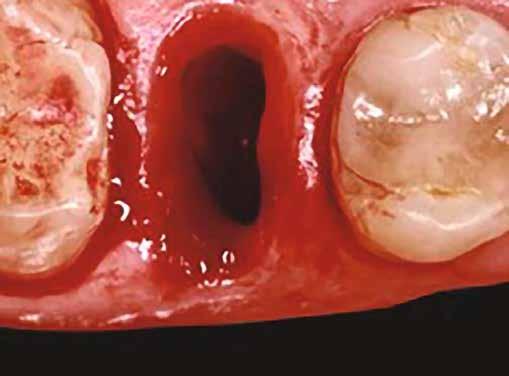

1. ábra: A műtét előtti szituáció, megfigyelhető az implantátumok közötti konkáv terület, ahova könnyen beragad az ételmaradék, és könnyen kialakul a periimplantitis.

Egy 47 éves páciens jelentkezett nálunk egy alsó, hátsó foghiánnyal, ahol jelentős csontfelszívódást tapasztaltunk a moláris fogak korábbi eltávolítása miatt (1. ábra). Két implantátum körül is volt ínyrecesszió, illetve a keratinizált íny mennyisége minimális volt (kevesebb, mint 1 mm). 4 hónappal az implantációt követően ínykorrekciót végeztünk.